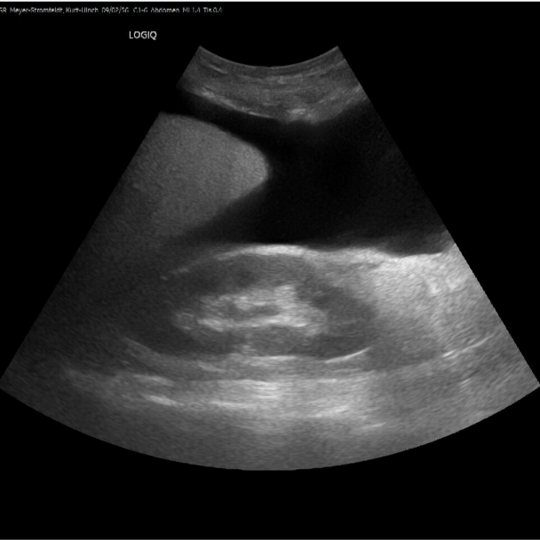

In comparison to other imaging techniques, ultrasound has relatively low technical requirements. Therefore, it can be utilised for clinical evaluation wherever the patient is being treated. This eliminates high costs and logistical constraints and professional diagnostics can be offered to the broad, financially disadvantaged rural population. Point-Of-Care-Ultrasound (POCUS) is used by clinicians to answer a specific clinical question to direct patient care and management. POCUS is relatively easy to learn and can be performed using standardised protocols, with findings being highly recognisable. In addition to the confirmation of an acutely treatable diagnosis, there is thus also a low-threshold and cost-effective initial assessment of the patient.

POCUS can be used for infectious diseases such as pneumonia, tuberculosis or schistosomiasis, as well as for non-communicable diseases such as cancer and liver cirrhosis or emergencies such as heart failure or trauma. Using POCUS can rapidly narrow differential diagnosis, shorten time to definitive treatment, reduce failure and complication rates during procedures and improve patient satisfaction. POCUS is therefore a relevant innovation and serves to optimise medical care for the financially disadvantaged population.